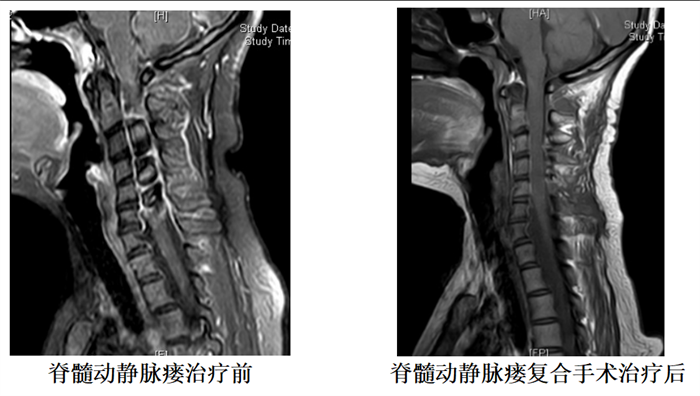

开展了脑中线部位诸如丘脑、松果体区肿瘤、脑干海绵状血管瘤高难度肿瘤手术,熟练运用Kawase入路切除跨幕上下神经肿瘤,Poppen入路经幕上切除小脑上蚓部血管母细胞瘤等高难度手术。对出血性脑血管病有深入的研究,有超过2000例颅内动脉瘤及动静脉畸形等脑血管病介入治疗成功经验,尤其擅长复杂动脉瘤及血管畸形的介入手术及开颅手术治疗,是省内屈指可数的能同时开展出血性脑血管病介入治疗及开颅手术的科室之一。独立开展颈动脉内膜剥脱术多年,已完成3200余例内镜辅助下脑出血手术。